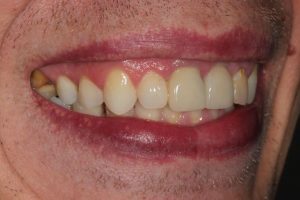

Upper Front Tooth Implant

This patient had broken their upper front tooth and the exisitng dental crown had fallen off. The underlying root was unfortunatley irreparable.

The dental root was subsequently removed and an implant placed at the same time. The implant had a temporary crown placedon the same day.

The ‘After’ photos shows the final crown that was made after 3 months. The implant crown was made to match the form and colour of the exisiting teeth to give an overall natural aesthetic finish.